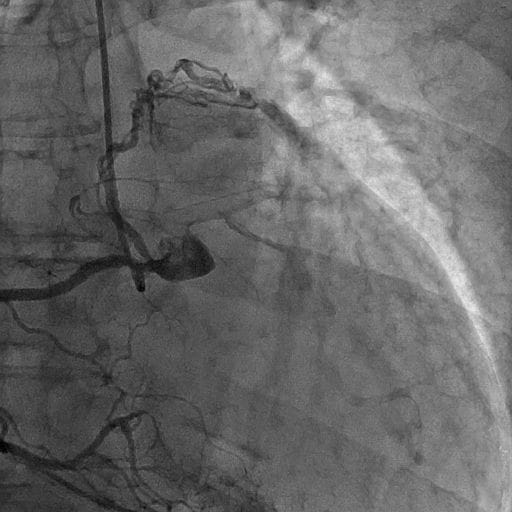

図5.冠動脈造影(右冠動脈)AP拡張期

右冠動脈造影にて右冠動脈肺動脈瘻を認める。

図6.冠動脈造影(右冠動脈)AP収縮期